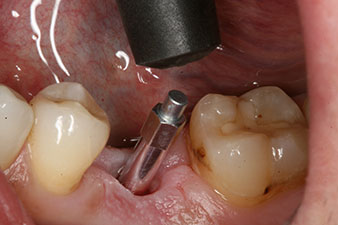

El torque en el momento de la carga mecánica fue de 43 Ncm. Asimismo, después de atornillar un poste de medición especial adaptado al sistema de implante (SmartPeg), el valor ISQ se determinó con la sonda del módulo Osstell ISQ de W&H.

Este módulo Osstell ISQ que se encuentra disponible como accesorio para la unidad Implantmed de W&H y se acopla al motor de implantes (véase figura 11). El valor ISQ adimensional fue de 64 justo en el momento de la inserción en la dirección bucovestibular y de 68 en la dirección mesiodistal (valor máximo = 100).